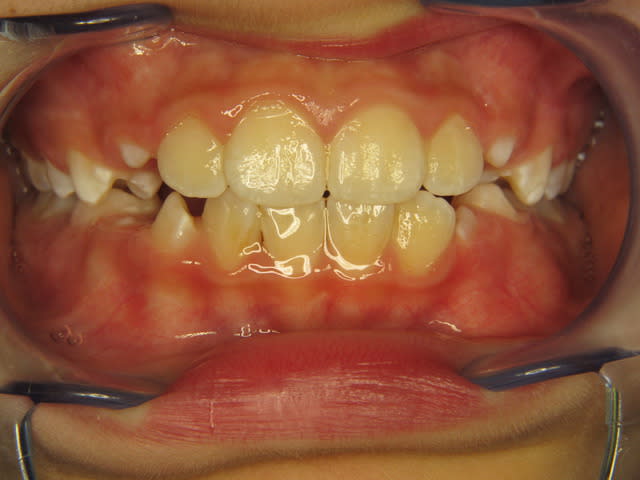

Enfant de 9ans avec déglutition infantile, résultat au bout de 4 mois de port de T4K. Et dire que l'ortho voulait le baguer à 12 ans!